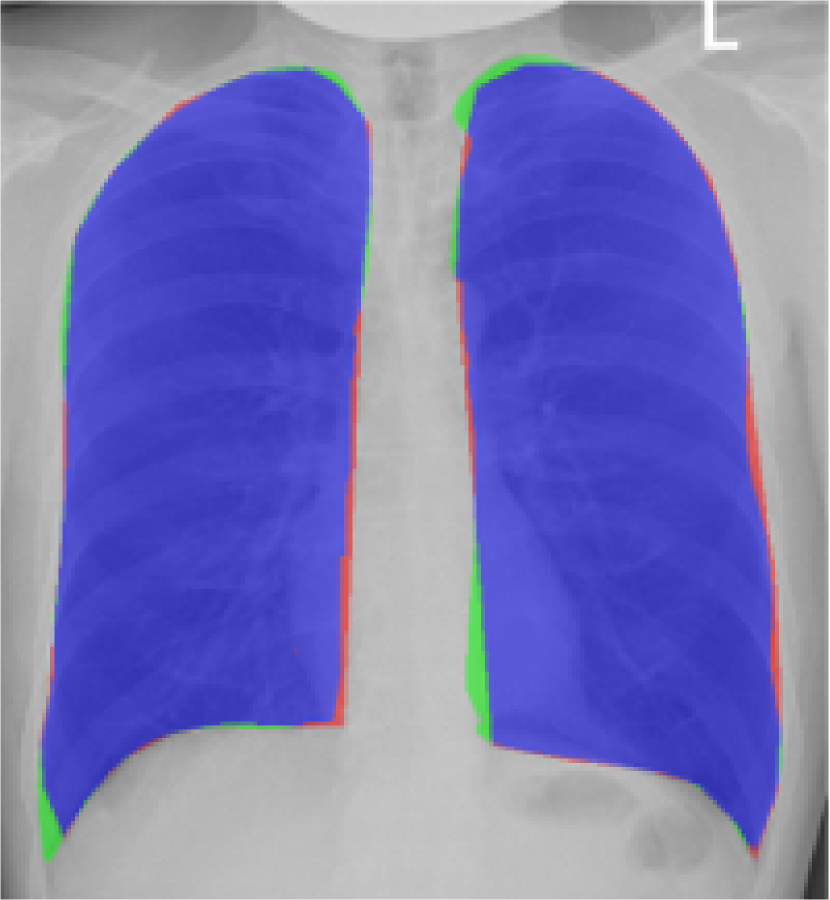

Fig. 9 presents the qualitative results of performing the lung segmentation using the proposed pipeline (ESL+MaShDL). The figure provides a visual insight on how inclusion of retro-cardiac region results in the segmentation label that is independent to the shape and structural changes in the close-by anatomical structures such as heart. For comparison purposes, similar qualitative results for the lung field labels obtained using the method proposed in [11] are provided in Fig. 10. As predicted before, the shape specificity is not preserved for the lung field labels obtained using [11]. This is further evident through the results presented in Table II. Moreover, unlike the proposed method, the U-net architecture uses an overlapping-based objective function (e.g., cross-entropy) which provides satisfactory results in cases with reduced shape variability. However, in the particular case of thoracic radiographs, the lung field labels without retro-cardiac space present higher shape variability than those observed when including this region. This could be a possible explanation of a slightly better overlapping-based performance (i.e., Overlap and DSC) by U-Net [11] when including the retro-cardiac space than without including it.